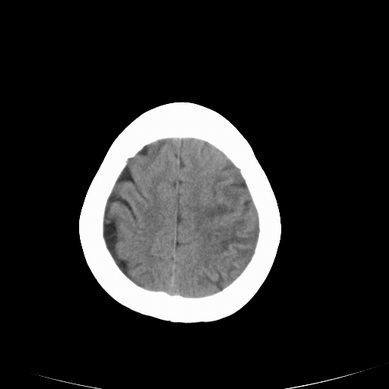

以下是引用jsgdoctor在2008-7-16 23:11:00的发言:[br]左侧大脑中动脉供血区脑梗塞